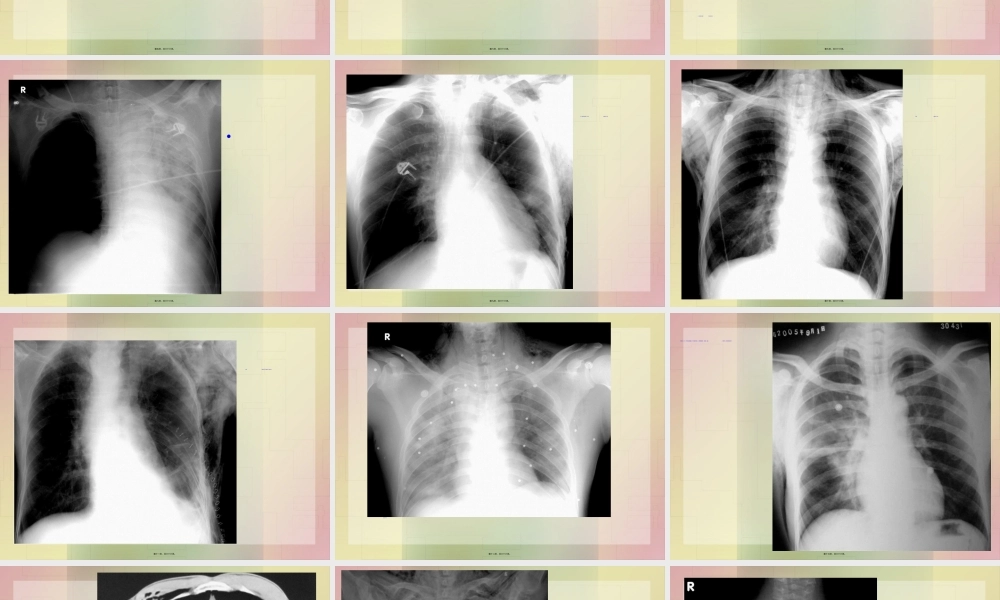

胸部胸部(xiōnɡbù)(xiōnɡbù)外外伤伤第一页,共六十六页。病理(bìnglǐ)与临床•肋骨骨折比较常见(chánɡjiàn),可为单发骨折,也可为多发骨折,还可为单一肋骨的多处骨折。以3-10肋的腋部及背部多见。第二页,共六十六页。病理(bìnglǐ)与临床第三页,共六十六页。病理(bìnglǐ)与临床第四页,共六十六页。X线表现(biǎoxiàn)1.肋骨骨折本身第五页,共六十六页。X线表现(biǎoxiàn)肺挫伤第六页,共六十六页。X线表现(biǎoxiàn)1.纵隔气肿表现为纵隔两旁(liǎngpáng)平行于纵隔的气带样影。第七页,共六十六页。•第八页,共六十六页。•左下肺创伤性湿肺,左侧胸壁皮下气肿。第九页,共六十六页。•两侧胸壁皮下气肿第十页,共六十六页。•左侧胸部术后,胸壁皮下气肿形成第十一页,共六十六页。(jǐnɡbù)第十二页,共六十六页。患者男,37岁,外伤后右侧胸痛1天(被锚挤压伤)。患者除胸痛外,无咳嗽、咯血。患者否认“既往肺部疾病史”。第十三页,共六十六页。影像所见结合病史诊断右肺撕裂伤及肺血肿(肺气囊形成),右胸壁皮下气肿。第十四页,共六十六页。胸壁及纵隔(zònggé)气肿第十五页,共六十六页。•纵隔气肿。纵隔内见带状低密度影第十六页,共六十六页。纵隔气肿。气管旁见带状低密度影第十七页,共六十六页。•纵隔气肿上纵隔气管(qìguǎn)两旁均见带状低密度影第十八页,共六十六页。第十九页,共六十六页。纵隔(zònggé)及皮下气肿横膈连续(liánxù)征第二十页,共六十六页。第二十一页,共六十六页。第二十二页,共六十六页。肺血液循环肺血液循环(xuèyèxúnhuán)(xuèyèxúnhuán)障碍障碍性疾病性疾病肺水肿肺栓塞第二十三页,共六十六页。肺水肿的病理(bìnglǐ)与临床•肺水肿是肺部血管外液体的增多,过多的液体积聚在肺间质和终末气腔内。根据肺水肿的发生机制,临床分为以下几类:①毛细血管(máoxìxuèɡuǎn)内静水压升高引起的肺水肿,如心源性肺水肿;②毛细血管(máoxìxuèɡuǎn)通透性增高引起的肺水肿;③其他原因如复张后肺水肿,高原性肺水肿等。第二十四页,共六十六页。X线表现(biǎoxiàn)1.间质型肺水肿•⑴肺血重新分布:两肺上野比下野的血管阴影粗。第二十五页,共六十六页。X线表现(biǎoxiàn)2.肺泡型肺水肿第二十六页,共六十六页。(dàpiàn)第二十七页,共六十六页。(fèipào)第二十八页,共六十六页。•肺泡(fèipào)性肺水肿第二十九页,共六十六页。(zhō...